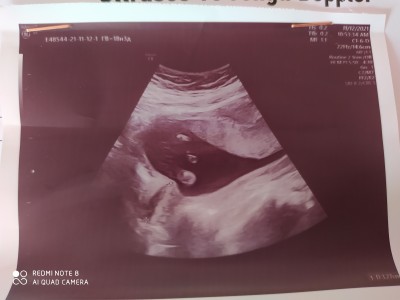

Bacakları görünüyor ama ben pipi göremedim kız bu görüntüye gorw

Muhtemelen üstten bişey gördü

Canım bir foto daha ekledim peki orda pipi gozukuyomu

Onları anlayamdım, ama doktor önden gormuştur erkekler hemen belli ediyor